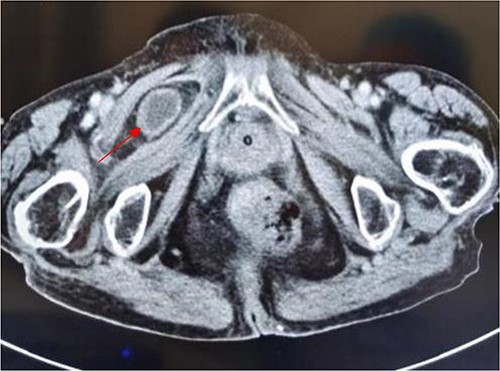

An 86-year-old female complained of constipation with abdominal pain, nausea, and vomiting for ˃2 weeks. The patient had defecated once, after conservative treatment with an enema in a local hospital, with less abdominal pain and no nausea or vomiting; hence, she was admitted to our hospital for further diagnosis and treatment. The patient’s body temperature was 36.8°C, pulse rate was 87 beats/min, respiration rate was 18 breaths/min, and blood pressure was 125/76 mmHg. The patient was conscious and had a thin appearance, and physical examination indicated that the abdomen was soft, and without tenderness and rebound pain. Routine blood examination showed that hemoglobin was 87 g/L and hematocrit was 28.3%. Abdominal computed tomography revealed the right lower abdominal small intestine protruding into the femoral triangle through the obturator; the upstream intestine was distended and expanded, and multiple fluid levels were observed in the intestinal lumen. Multiple lymph nodes were noticed in the abdomen and retroperitoneum; the large ones had a diameter of ~1 cm. Uneven thickening and enhancement of the local ascending colon were noted.

Computed tomography axis map showing the small intestine entering the femoral triangle (red arrow).